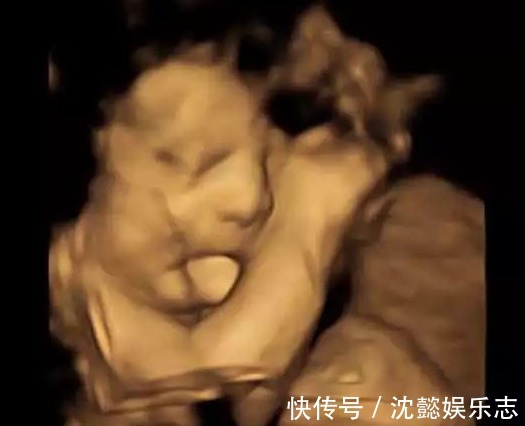

妈妈看到了怀孕27周的B超图像。那时,孩子一直吐舌头。母亲本以为孩子是在做鬼脸,妈妈还觉得很可爱,就把B超影像图在朋友圈发布了,但孩子出生的时候,孩子的样子也是吓了妈妈一跳,医生说这样的病情大概14万人才会有一个。

4月有媒体报道称,一名来自美国俄克拉荷马州的19个月大的男婴出生时舌头特别大,没办法自己收回嘴里。所以他不得不接受手术。目前,孩子的舌头还在恢复,希望孩子尽快学会说话。这个男孩的名字叫Baker Rose,因为他患有伯-韦综合症,这是一种罕见的过度生长障碍病,并且在8个月大时不得不接受剖腹产手术。新出生的外表让母亲Farah Rose感到惊讶,孩子的的舌头是正常人的两倍大,不能自己放进嘴里,这让她想起了她在怀孕第27周看到的 B超检查图像,当孩子的舌头在嘴外时,她认为孩子正在做鬼脸,感觉很可爱,还把B超图像发到了朋友圈 。